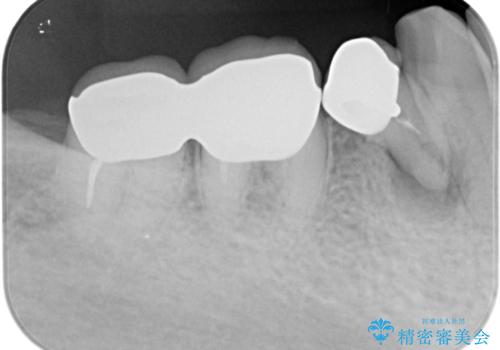

- 他院で右下小臼歯が保存不可能と言われ来院。当院の判断でも残念ながら抜歯となり、欠損部は抜歯後ブリッジにしました。右下奥2本が連結されていたため、そこは各々切り離した形で被せ物のやり替えも行っています。

- 約60万円 右下④5⑥:ジルコニアクラウンブリッジ 11万円×3 仮歯 1万円×3 根管治療費用別途費用は治療当時の料金となります

抜歯後3か月ほど仮歯で生活していただき、欠損部の歯肉の状態が安定してからブリッジを入れています。